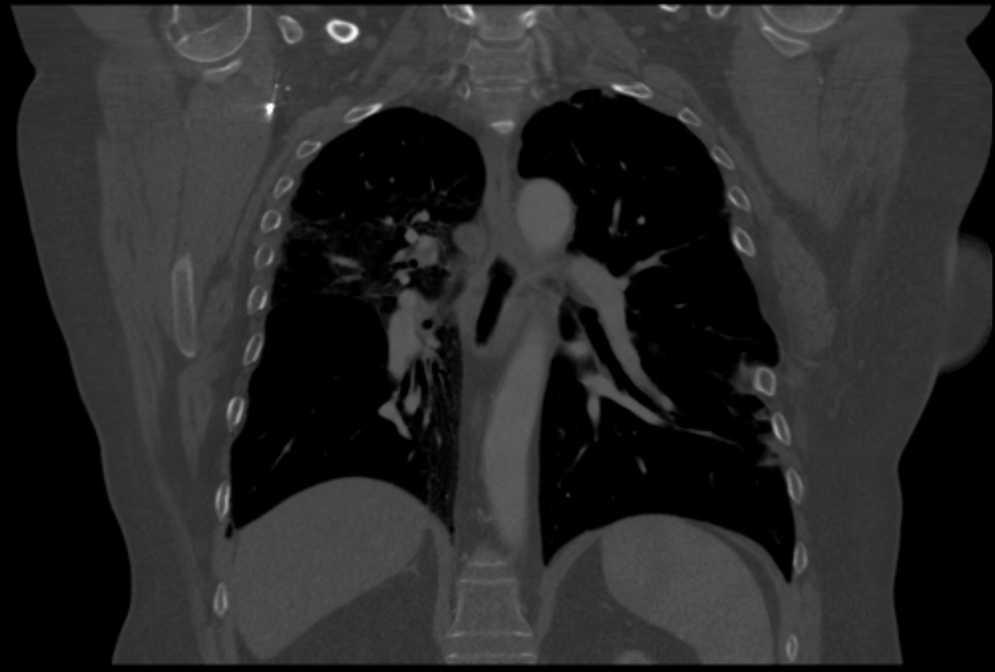

Pulmonary vein obstruction is usually an early complication, occurring during the first few hours after transplantation, and causes severe symptoms. Marked hypoxia, pulmonary edema, and pulmonary infiltrates are observed. If the lower lobe is more severely affected, a high suspicion for such a complication is warranted, and an early additional diagnostic test should be ordered. The initial test should be a transthoracic or transesophageal echocardiogram, in spite of this test being only useful for diagnosis when performed by an experienced operator, due to a challenging visualization and interpretation after recent surgery 6. Alternatively, chest CT angiography can be used, which also allows artery suture and distal vascularization to be assessed and reconstructions to be produced. CT angiography establishes the diagnosis in most cases. Anticoagulation using heparin and clinical course monitoring is used to manage partial thromboses and stenoses. In the event of a complete vein obstruction or a poor course, in patients with a very recent surgery, re-transplantation or lobectomy for double-lung transplantations, may be needed. If the patient is in a stable condition, several days have elapsed, and anatomic characteristics are favorable, an angioplasty with dilation and stent implant can be considered.

Figure 3. Coronal view in CT angiography showing complete lower pulmonary vein obstruction after left lung transplantation.

Figure 4. CT image showing extensive lung infiltrates in lower left lobe resulting from lower pulmonary vein obstruction.